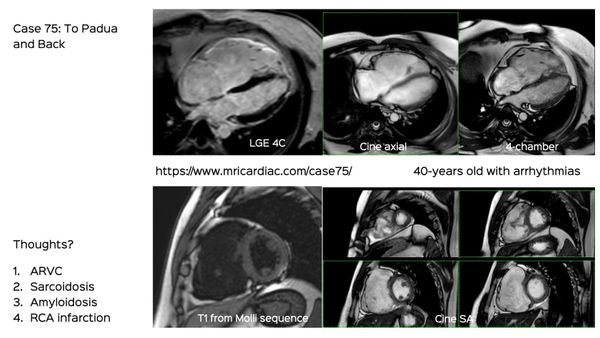

The new 2020 Padua criteria explained